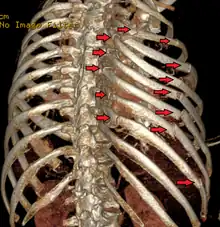

El diagnóstico se basa en la sintomatología y la exploración del paciente que detecta una serie de signos específicos. Las pruebas complementarias más utilizadas para confirmar el diagnóstico son la radiografía de tórax y la tomografía axial computarizada en caso de traumatismos graves.[2]